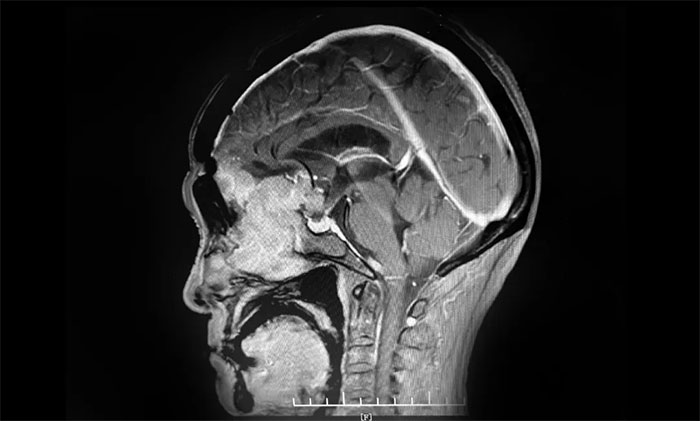

▲ 通过增强磁共振影像,可见前颅底嗅沟脑膜瘤,体积巨大

头部增强磁共振影像显示,患者前颅底嗅沟脑膜瘤体积约6.7*6.4*5.1公分,大如鸭蛋,属巨大脑膜瘤,瘤体一小部分已经延伸侵犯到筛窦内。经评估并充分告知手术风险后,7月9上午,李志强主任为患者实施巨大脑膜瘤切除手术。